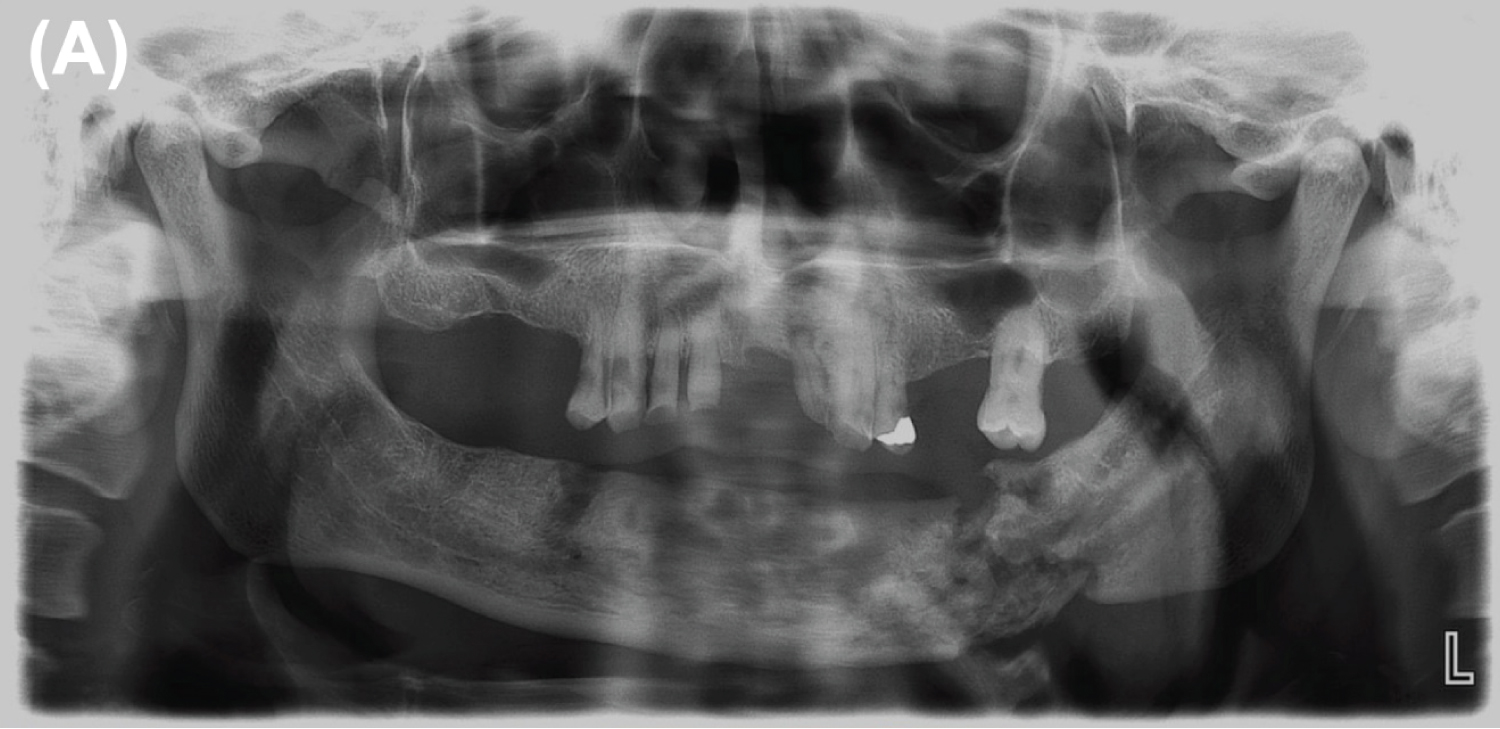

The extraoral examination revealed a volume increase and a cutaneous fistula with purulent drainage in the left submandibular area. On intraoral examination, an upper partial edentulism with multiple cervical caries, and a mandibular edentulism with an increase in volume in the left alveolar ridge, with bone exposure in the tooth area 3.6. Also, a 3 mm mobile bone sequestration was observed in the lower lingual area, and a vestibular bone exposure of 2 mm. The patient was hospitalized for decompensated IRDM and intravenous antibiotic therapy with Ceftriaxone 2 gr/day and Clindamycin 600 mg every 8 hours. An Orthopantomography (OPG) was requested, which revealed diffuse radiolucent areas compatible with pathological mandibular fracture and basilar bone sequestration (Figure 1). A computerized axial tomography (CT) revealed diffuse hypo and hyperdense areas with destruction processes and multiple bone sequestration that reached the basilar border. Besides confirming ORN diagnosis and ruling out tumor recurrence at the affected site, a positron emission tomography (PET-CT) was requested, which showed isolated bone fragments compatible with sequestration and bone metabolic hyperactivity suggestive of osteomyelitis, confirming the diagnosis of ORN Notani stage III (Supplementary Figure 1B, Supplementary Figure 1C and Supplementary Figure 1D). An angio-CT of inferior extremities was requested to evaluate the eventual mandibular reconstruction with fibula free flap. The images showed advanced multiple atheromatosis, which within the context of the multiple comorbidities of the patient contraindicated this procedure.

Figure 1: Diagnostic OPG where a fracture in the pathological bone and the presence of multiple bone sequestration are observed. View Figure 1